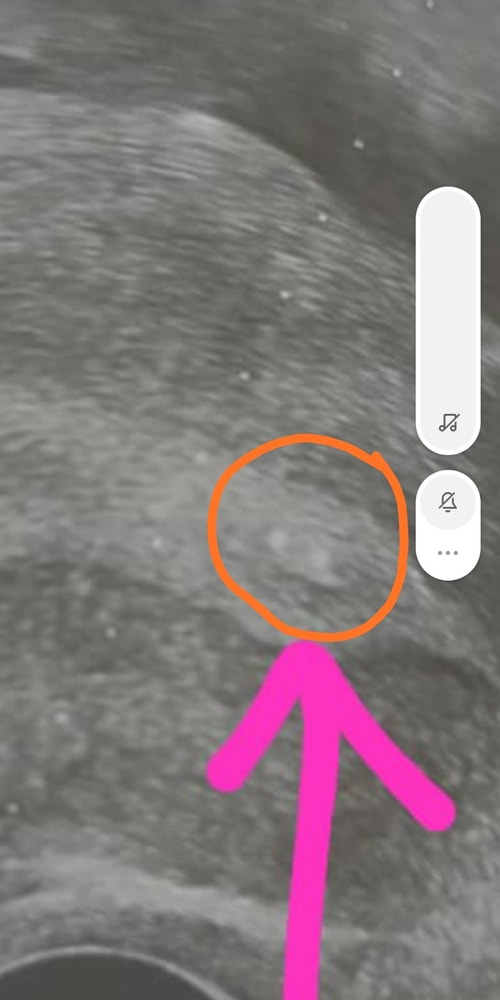

Дорогие девочки, смотрю на снимок после переноса и вижу что в отличие от первого раза где точечки на распечатанном УЗИ при подсадке были в середине матки сейчас они прям у самого низа матки где цервикальный канал

Мог ли доктор подсадить так низко , на след день дпп1 у меня выпали два крупных круглых кровяных сгустка в яичном белке круглой формы я в смятении могли ли просто выпасть эмбрионы и почему они подсажены так низко?

напишите фамилию врача и куда вам подсадил. Я расстроилась очень. Доктор отвечает что на фото просто не видно место подсадки но это не первый мой крио и мне всегда сажали выше в центр матки тут скажите честно ошибка врача?